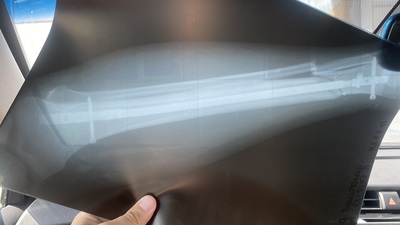

Вот одна из систем для интрамедуллярного остеосинтеза. Конструкция сверху - она снаружи, а сам стержень внутри бедренной кости

Длинная под углом - это отвертка, которая вкручивает винты в стержень. На самом стержне есть несколько отверстий для винтов, которыми он фиксируется. Чтобы вставить стержень внутрь кости, нужно сделать канал внутри нее.